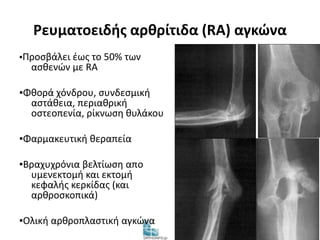

Ρευματοειδής αρθρίτιδα (RA) αγκώνα

▪Προσβάλει έως το 50% των

ασθενών με RA

▪Φθορά χόνδρου, συνδεσμική

αστάθεια, περιαθρική

οστεοπενία, ρίκνωση θυλάκου

▪Φαρμακευτική θεραπεία

▪Βραχυχρόνια βελτίωση απο

υμενεκτομή και εκτομή

κεφαλής κερκίδας (και

αρθροσκοπικά)

▪Ολική αρθροπλαστική αγκώνα